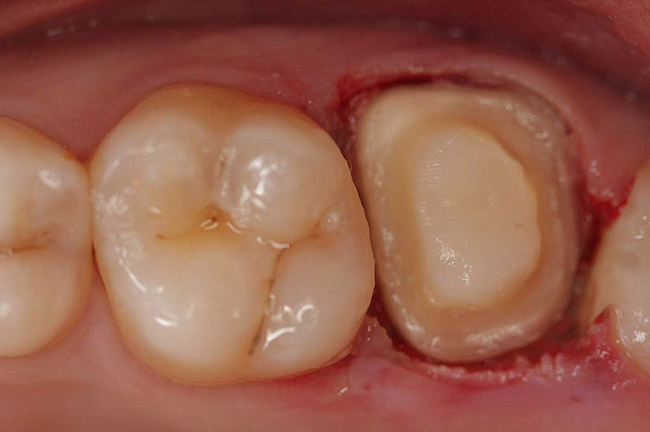

Figure 10  Final tooth preparation to accept a PFM crown.

Figure 10

Figure 11  Final porcelain-fused-to-metal crown.

Figure 11

Core build-up was completed with Absolute Dentin™ (Parkell, www.parkell.com) dual-cure high-strength core composite. There are variations on color and how materials cure. For example, Light-Core™ (Bisco, www.bisco.com) is a light-cured blue material, Encore® (Centrix, www.centrixdental.com) is a self-cure white material, and Para Core (Coltène Whaledent, www.coltene.com) is a dual-cure white or dentin-colored material. Material was placed directly and light-cured for 40 seconds (Figure 9). Final preparation for a PFM was completed (Figure 10). The final crown was placed (Figure 11).